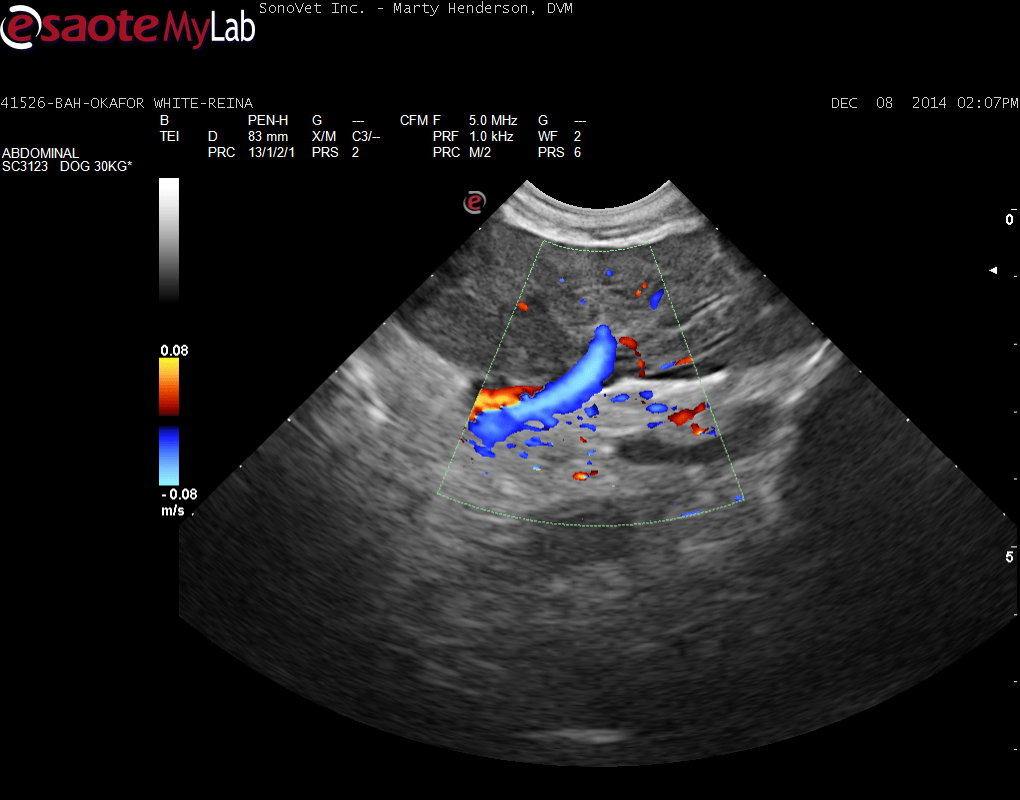

A 6-year-old female Labrador was presented for evaluation of loose stools and weight loss. Abnormalities on serum biochemistry were elevated liver enzyme activity and hypoalbuminemia. On survey thoracic radiographs, a mild interstitial pulmonary pattern was evident.